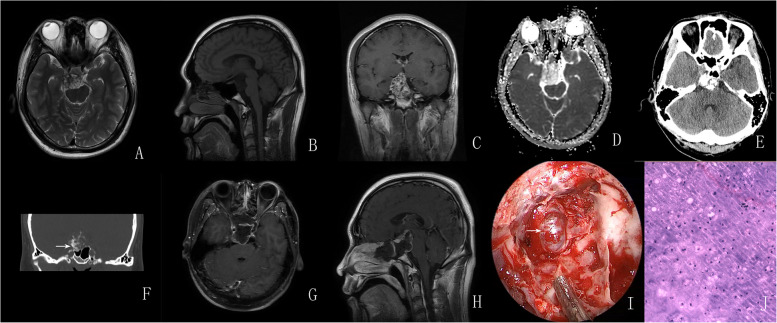

Conclusions: The preoperative diagnosis of sellar chondrosarcoma remains challenging and often requires differentiation from chordoma, INPA, or craniopharyngioma. When a calcified mass in the sellar region presents with intact or slightly disturbed anterior pituitary function, heterogeneous enhancement and no diffusion restriction on Magnetic Resonance Imaging(MRI) sequences, and surrounding bony destruction and bony attachment on Computed Tomography(CT) scans, a chondrosarcoma should be suspected preferentially. Complete resection is the optimal goal for the management of sellar chondrosarcoma, but adjuvant radiotherapy and periodic follow-up should be highlighted.